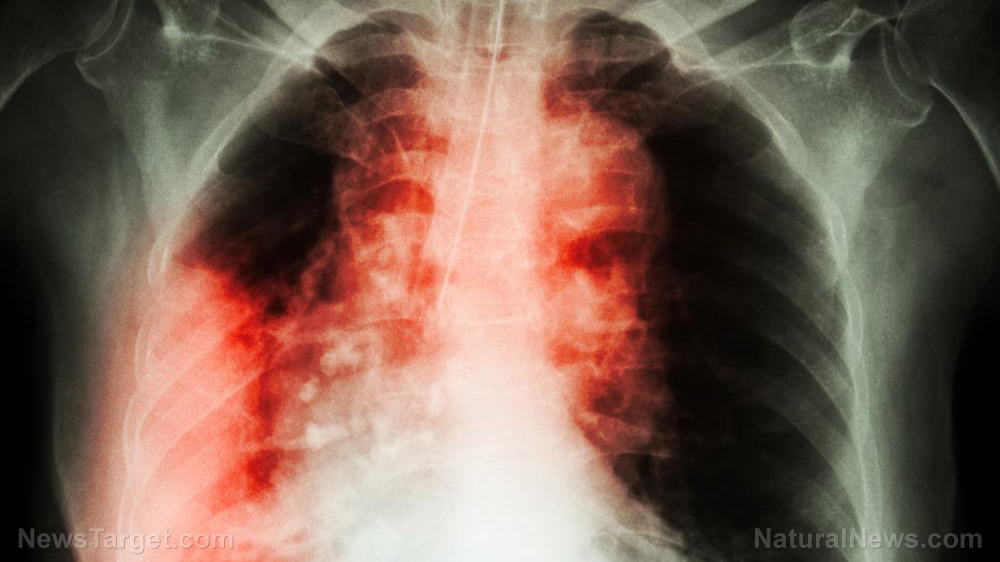

Cancer treatments HARM patients: Radiotherapy can cause aggravated lung injury – study

A Canadian research team announced that it has found the reason for the appearance of pulmonary fibrosis in a number of lung cancer patients who underwent thoracic radiotherapy. They found a connection between genes on a certain chromosome and the development of lung injuries triggered by radiation. The researchers were investigating chromosome 6, one of the 23 pairs of DNA molecules found in humans. This particular chromosome contained around six percent of the total genetic material in a cell, including more than 100 genes connected to the human immune system. University of British Columbia, Okanagan (UBC Okanagan) researcher Christina Haston reported that chromosome 6 was somehow connected to the risk of radiation-induced pulmonary fibrosis. Certain genetic material in the chromosome appeared to dictate whether or not the lung would sustain additional injuries after undergoing radiation therapy for lung cancer. "Currently, 50 per cent of cancer patients in Canada receive radiation therapy as part of their treatment course," Haston said. "In addition to effects on the tumour, up to 30 per cent of these patients develop side effects to this treatment, or injuries to non-tumour tissue." (Related: This African shrub shows remarkable anticancer potential.)

Pulmonary fibrosis is a progressive disease caused by the scarring of injured lung tissue. The scar tissue that developed on the organ is thicker and stiffer than healthy tissue. Fibrosis hampers the normal expansion and contraction of the lung. This reduces the amount of oxygen that could be drawn with each breath, which in turn decreases the amount of oxygen available for use by the body. There are lung cancer patients who experience pulmonary fibrosis after getting exposed to radiation, such as during thoracic radiotherapy treatment. Other patients suffering from different types of cancer develop this lung condition after taking Bleomycin (Blenoxane), a pharmaceutical drug used for chemotherapy. "One of the limiting side effects of thoracic radiotherapy is the development of pulmonary fibrosis in a susceptible subpopulation of treated patients," Haston remarked. "However, the specific pathways contributing to fibrosis susceptibility in radiotherapy patients remain unidentified." Previous studies have suggested that pulmonary fibrosis is in part attributed to white blood cells. One of the natural defenses of the body, these immune cells move throughout the body in search of pathogens. Some of the genes in chromosome 6 oversaw immune responses, including white blood cells. Haston came to believe there was a connection between the chromosome and the risk of fibrosis.